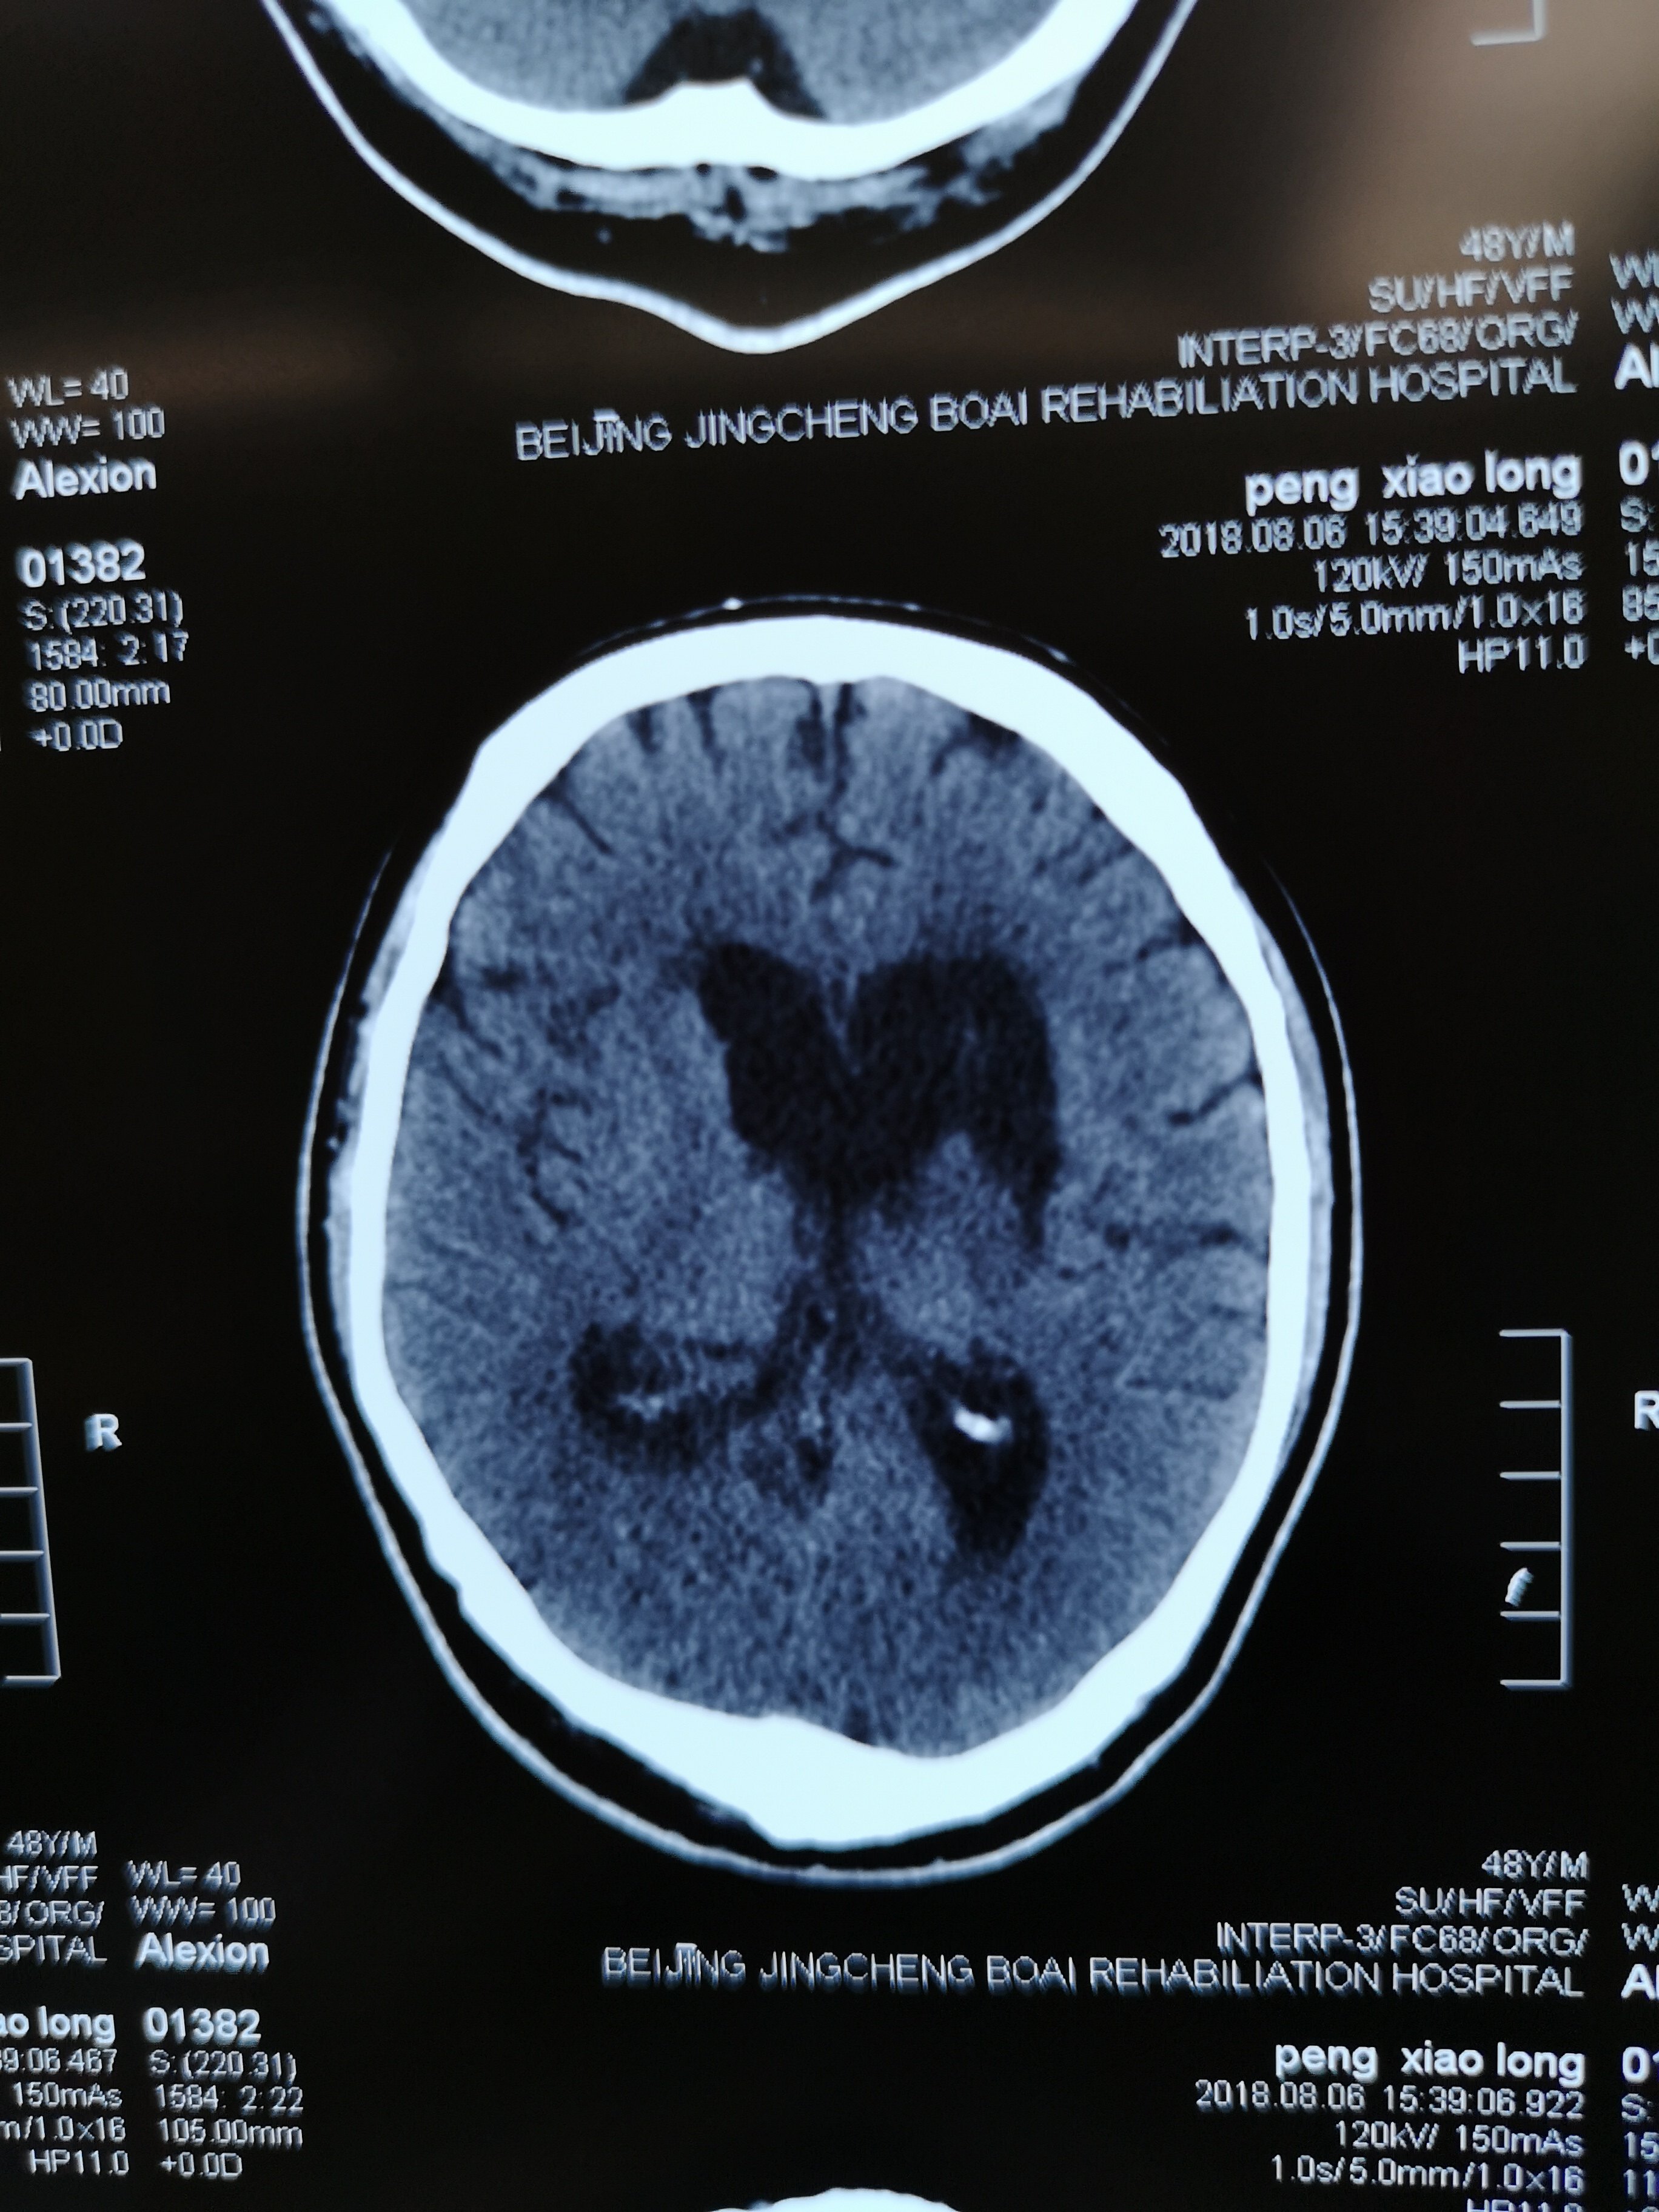

脑干出血6毫升昏迷20天的病人,从深圳转

醒7-左侧脑出血破入脑室后清醒,再度脑干出血陷入昏迷不醒 - 好大夫